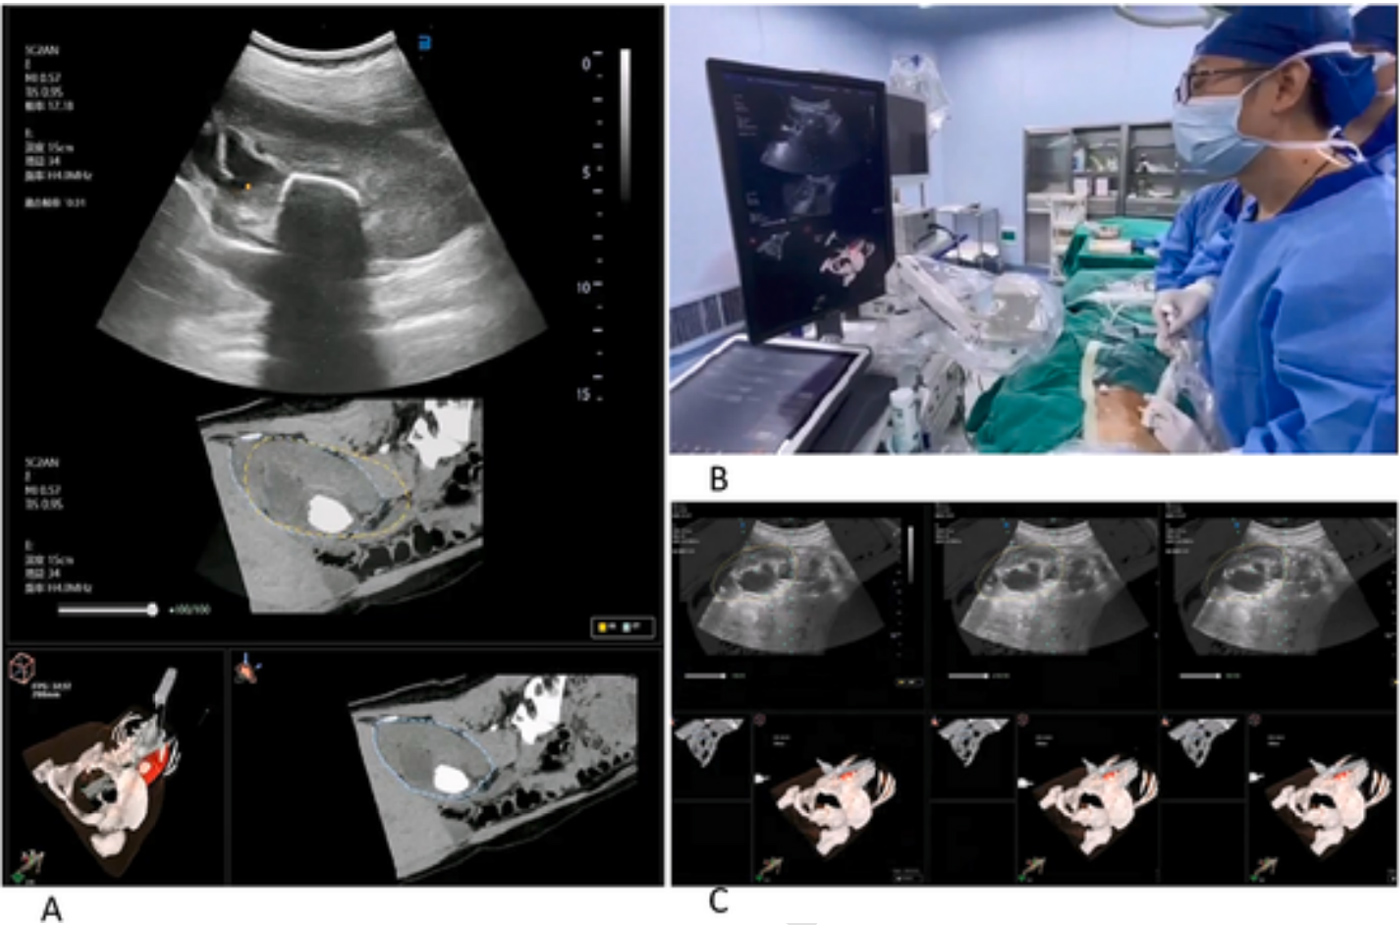

Fig. 1. Clinical application of ultrasound-CT image fusion technology in percutaneous nephrolithotripsy